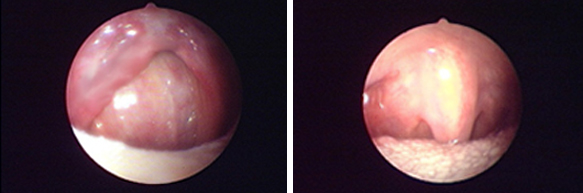

耳鼻喉科

經(jīng)典案例: